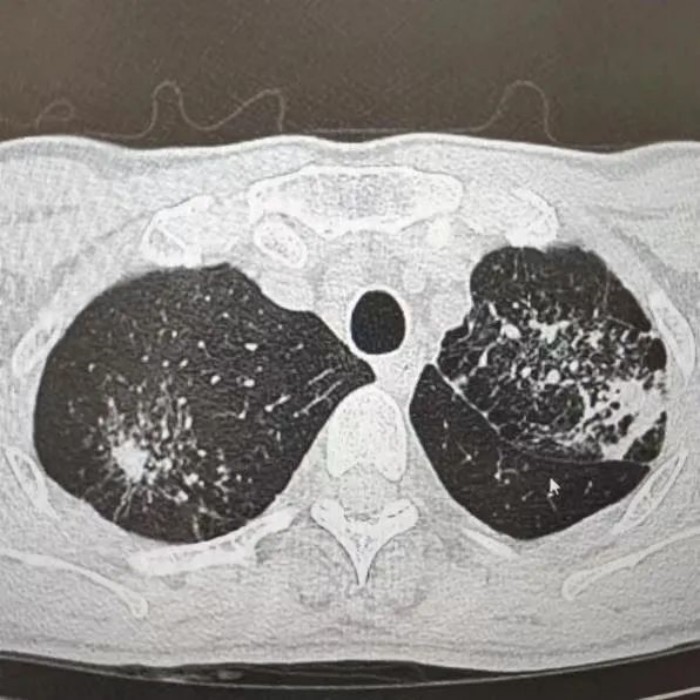

很快,CT報告提示“升結(jié)腸、回盲部及回腸末端腸壁增厚伴局部淋巴結(jié)腫大,考慮腸結(jié)核”。之后,進(jìn)一步做了胸部CT檢查,提示“肺部浸潤灶:肺結(jié)核考慮”。

經(jīng)過痰化驗(yàn)及腸鏡檢查病理活檢,葉師傅被確診為“肺結(jié)核、腸結(jié)核伴腸梗阻”。